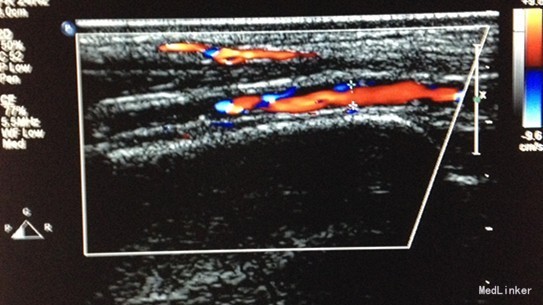

入院查体:双侧足背动脉搏动差,皮温稍凉。 辅助检查:血脂分析:血清总胆固醇测定TC5.77mmol/L。血浆糖化血红蛋白测定HbA1C10.20%。双髋关节骨密度测定,诊断意见:髋关节骨量减少。腰椎骨密度测定,诊断意见:腰椎骨质疏松。左下肢动脉彩色多普勒超声,诊断意见:左侧下肢动脉硬化闭塞症改变,左侧足背近段、胫前及胫后动脉阻塞性病变,左侧足背近段、胫前及胫后动脉血流速度减低。右下肢动脉彩色多普勒超声,诊断意见:右侧下肢动脉硬化闭塞症改变,右侧胫前、足背动脉及胫后动脉阻塞性病变,右侧胫前、足背及胫后动脉血流速度减低或未测及。左颈动脉彩色多普勒超声,诊断意见:左侧颈动脉内膜增厚、欠光滑,左侧颈动脉血流速度正常范围。右颈动脉彩色多普勒超声+图文报告,诊断意见:右侧颈动脉硬化样改变,右侧颈内动脉内径略细,右侧颈内动脉颅外段血流速度及频谱形态异常。颅脑CT平扫(64排),诊断意见:双侧基底节区小缺血灶。 OGTT 0 30 60 120 180 葡萄糖(mmol/L) 8.36 9.56 14.06 15.70 13.19 C 肽(pmol/L) 528.99 518.54 810.39 1083.19 54.89 胰岛素(mIU/L) 26.02 4.77 52.61 63.73 968.48 腹部彩超及膀胱残余尿量:脂肪肝,左肾集合系统分离,排尿后略缩小。残余尿量23ml。

随访:一个月后患者行左下肢自体骨髓干细胞移植,术后左下肢皮温皮色可,无感觉异常,多普勒血流仪可在左下肢闻及足胫后动脉闻及血流搏动音。 讨论:糖尿病、高血压均可发生大血管并发症,该患者病史长,已出现下肢动脉闭塞,内科疗效差,可采取外科治疗。